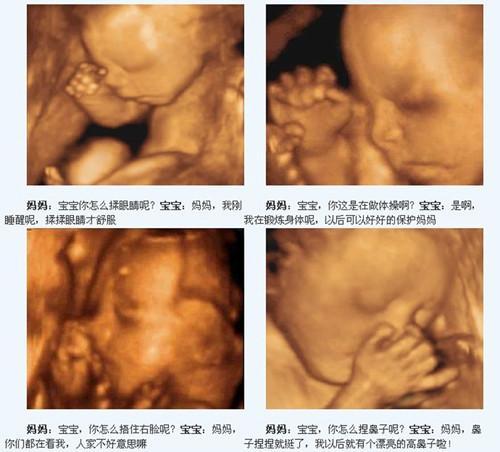

看到一张照片很有意思,是孕妈妈和胎儿的对话:

妈妈:宝宝,你怎么揉眼睛呢?

宝宝:妈妈,刚睡醒呢,揉揉眼睛才舒服。

妈妈:宝宝,你这是在做体操啊?

宝宝:是啊,我在锻炼身体呢,以后可以好好的保护妈妈!

妈妈:宝宝,你怎么捂住右脸呢?

宝宝:妈妈,你们都在看我,人家不好意思嘛!

妈妈:宝宝,你怎么捏鼻子呢?

宝宝:妈妈,鼻子捏捏就挺了,我以后有个漂亮的高鼻子啦!